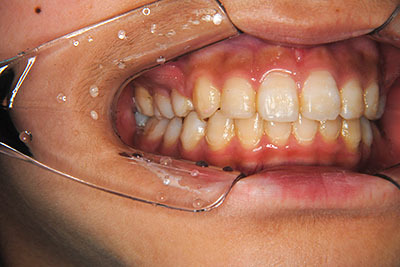

小学生高学年や中高生で矯正治療を考えている方へ

歯が乳歯から永久歯に生え変わった小学生高学年や、中高生でも矯正治療に手遅れということは全くありません。

成長中の顎の骨を矯正できたり、この時期の矯正はおとなになってから矯正治療を始めるよりも短期間で済むことがほとんどです。当院だとおおよそ1年で動的治療(マルチブラケット装置をつける期間)が終わることが多いです。